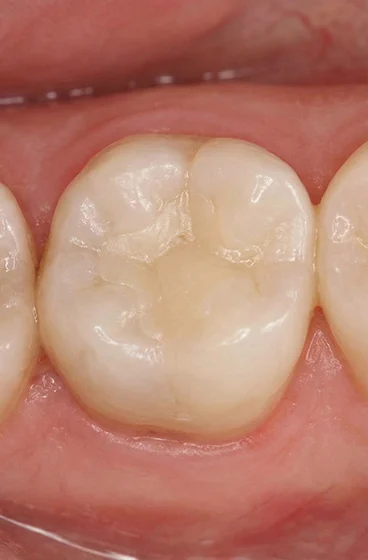

Brush twice a day with fluoridated toothpaste and floss gently around the filled tooth to limit plaque buildup. Avoid chewing ice or hard candies, and reduce sugary snacks to lower the risk of new decay around the filling. If sensitivity lasts or you notice a crack, contact us promptly. With steady care, dental fillings can last for many years.